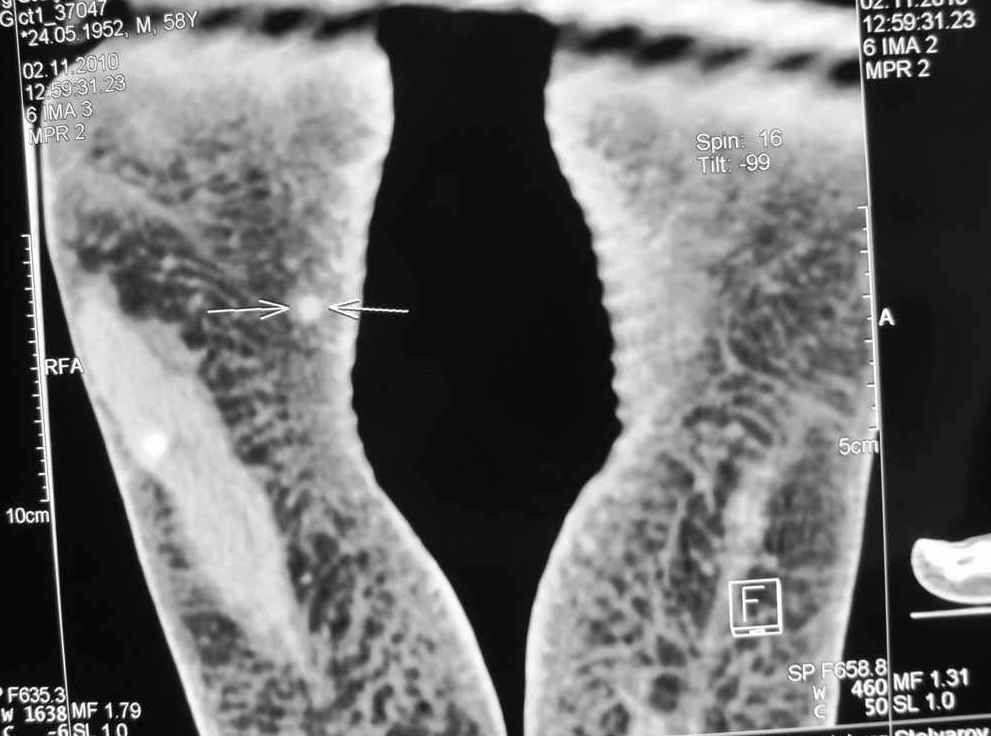

Мужчина 58 л. месяц назад наступил на камень, после того, как прошли боли, почувствовал уплотнение с медиальной стороны правой стопы.

Сделал КТ 02.11.2010 г.

Пальпаторно: определяется уплотнение размеры с горошину (0,3 Х 0,2), при пальпации безболезненно, малоподвижное. Кожные покровы в области уплотнения не изменены.

Мне по снимкам кажется, что это маленькая кальцифицированная гематома. Я бы убрал.